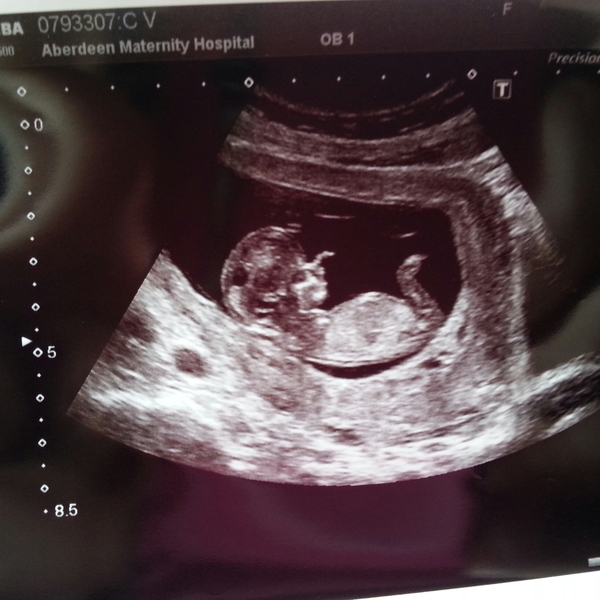

Hopefully this attachment works!

We declined nt screening - nt measurement was 1.4 and we didn't want to do bloods so left it at that

Now due 14/3 but have a date to go back to book my section for 39 weeks

Lovely scan pic toast

Nice pic toast

Toast your scan picture is beautiful